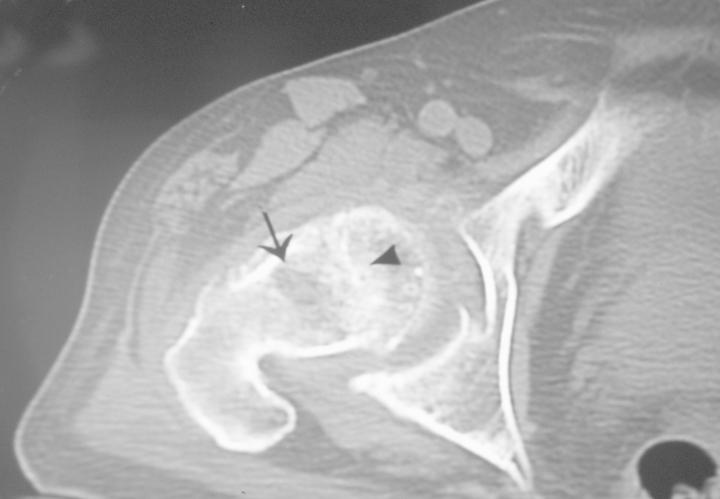

Avascular necrosis of the femoral head (AVN) is an increasingly common cause of musculoskeletal disability, and it poses a major diagnostic and therapeutic challenge. Although patients are initially asymptomatic, AVN usually progresses to joint destruction, requiring total hip replacement, usually before the fifth decade. Avascular necrosis is characterized by osseous cell death due to vascular compromise. Avascular necrosis of bone results generally from corticosteroid use, trauma, pancreatitis, alcoholism, radiation, sickle cell disease, infiltrative diseases (e.g. Gaucher's disease), and Caisson disease. The most commonly affected site is the femoral head and patients usually present with hip and referred knee pain. The aim of diagnostic imaging procedures in avascular femoral head necrosis is to provide the patient with a stage-adapted therapy. Therefore, a differentiated diagnostic work-up is needed. Native radiography of the hip in two planes is still the first step. Over the past years, the diagnosis of femoral head necrosis has experienced tremendous improvement due to the use of MRI and CT scans. Because of these improvements the correct stage can be diagnosed early and the appropriate therapy can be initiated immediately. Today, MRI is the most sensitive diagnostic imaging procedure. CT scans can be particularly useful to exclude subchondral fractures. The use of bone scintigraphy is restricted to exceptional cases. In Europe, the ARCO classification of avascular femoral head necrosis has been widely accepted. In this overview, we describe the specific characteristics of the different diagnostic imaging procedures and illustrate them with appropriate imaging material.

股骨头缺血性坏死(AVN)是导致肌肉骨骼残疾的一个日益常见的原因,它带来了重大的诊断和治疗挑战。尽管患者最初没有症状,但AVN通常会发展为关节破坏,通常在50岁之前就需要进行全髋关节置换。缺血性坏死的特征是由于血管受损导致骨细胞死亡。骨缺血性坏死通常由使用皮质类固醇、创伤、胰腺炎、酗酒、辐射、镰状细胞病、浸润性疾病(如戈谢病)和减压病引起。最常受累的部位是股骨头,患者通常表现为髋部疼痛并伴有膝关节牵涉痛。股骨头缺血性坏死诊断成像程序的目的是为患者提供适合其分期的治疗。因此,需要进行差异化的诊断检查。髋关节的双平面X线平片仍然是第一步。在过去几年中,由于使用了MRI和CT扫描,股骨头坏死的诊断有了巨大改善。由于这些改进,可以早期诊断出正确的分期,并立即开始适当的治疗。如今,MRI是最敏感的诊断成像程序。CT扫描对于排除软骨下骨折特别有用。骨闪烁显像的应用仅限于特殊情况。在欧洲,股骨头缺血性坏死的ARCO分类已被广泛接受。在本综述中,我们描述了不同诊断成像程序的具体特征,并用适当的影像资料进行说明。